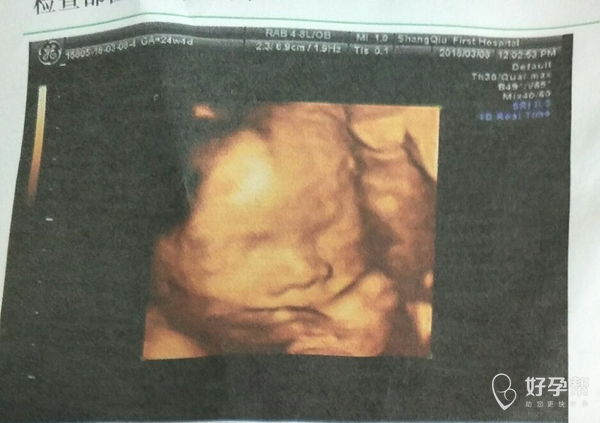

医生帮忙看看这个四维图

你好,有压迹一般都有期待缠绕,目前应该是属于孕中期,密切观察胎动,脐带绕颈可能会自行松开